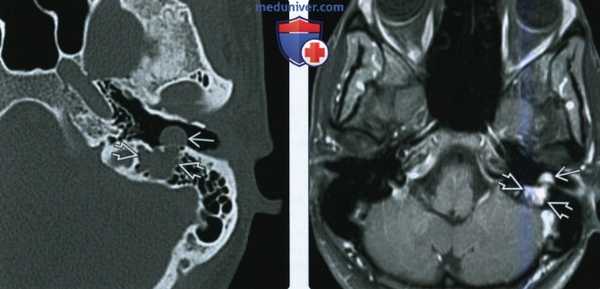

(Слева) При аксиальной КТ в костной окне определяется объемное образование в расширенной ямке коленчатого ганглия с распространением опухоли вдоль переднего барабанного сегмента ЧН VII со смещением слуховых косточек латерально. Наружная поверхность слуховой капсулы истончена ШЛН.

(Справа) При аксиальной МРТ Т1 С+ FS у этого же пациента визуализируется контрастирующаяся ШЛН, расположенная в коленчатом ганглии. Опухоль распространяется вдоль барабанного сегмента ЧН VII и во внутренний слуховой канал по лабиринтному сегменту ЧН VII. Обратите внимание на интрамуральную кисту медиально.